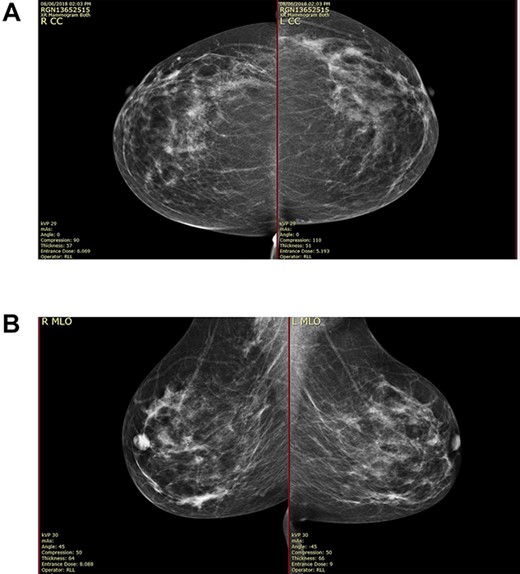

On clinical examination, there were tender nodularities in the upper outer quadrant of the right breast. The nipple looked thick and tender at the nipple tip, with punctate bleeding from different sites (P3) (Fig. 1). Examination on the left breast and both of the axillae were unremarkable. The mammogram reported segmental distribution of pleomorphic calcification on the right breast, which was widespread and was measuring up to 11 cm from the nipple posteriorly. The appearances of the calcifications were suspicious for malignancy (M4). There were benign appearing calcifications on the left breast as well (M2) (Fig. 2). On ultrasound (US), there was no discrete mass or suspicious feature seen in the right upper outer quadrant. However, there was a 10-mm deep-seated, round, abnormal-looking lymph node on the right axilla (U4), which could not be biopsied at the time due to a pulsating blood vessel overlying it [1] (Fig. 3).

(A) Mammography showed widespread segmental distribution of pleomorphic calcification on the right breast measuring up to 11 cm; (B) mammography showed widespread segmental distribution of pleomorphic calcification on the right breast measuring up to 11 cm.